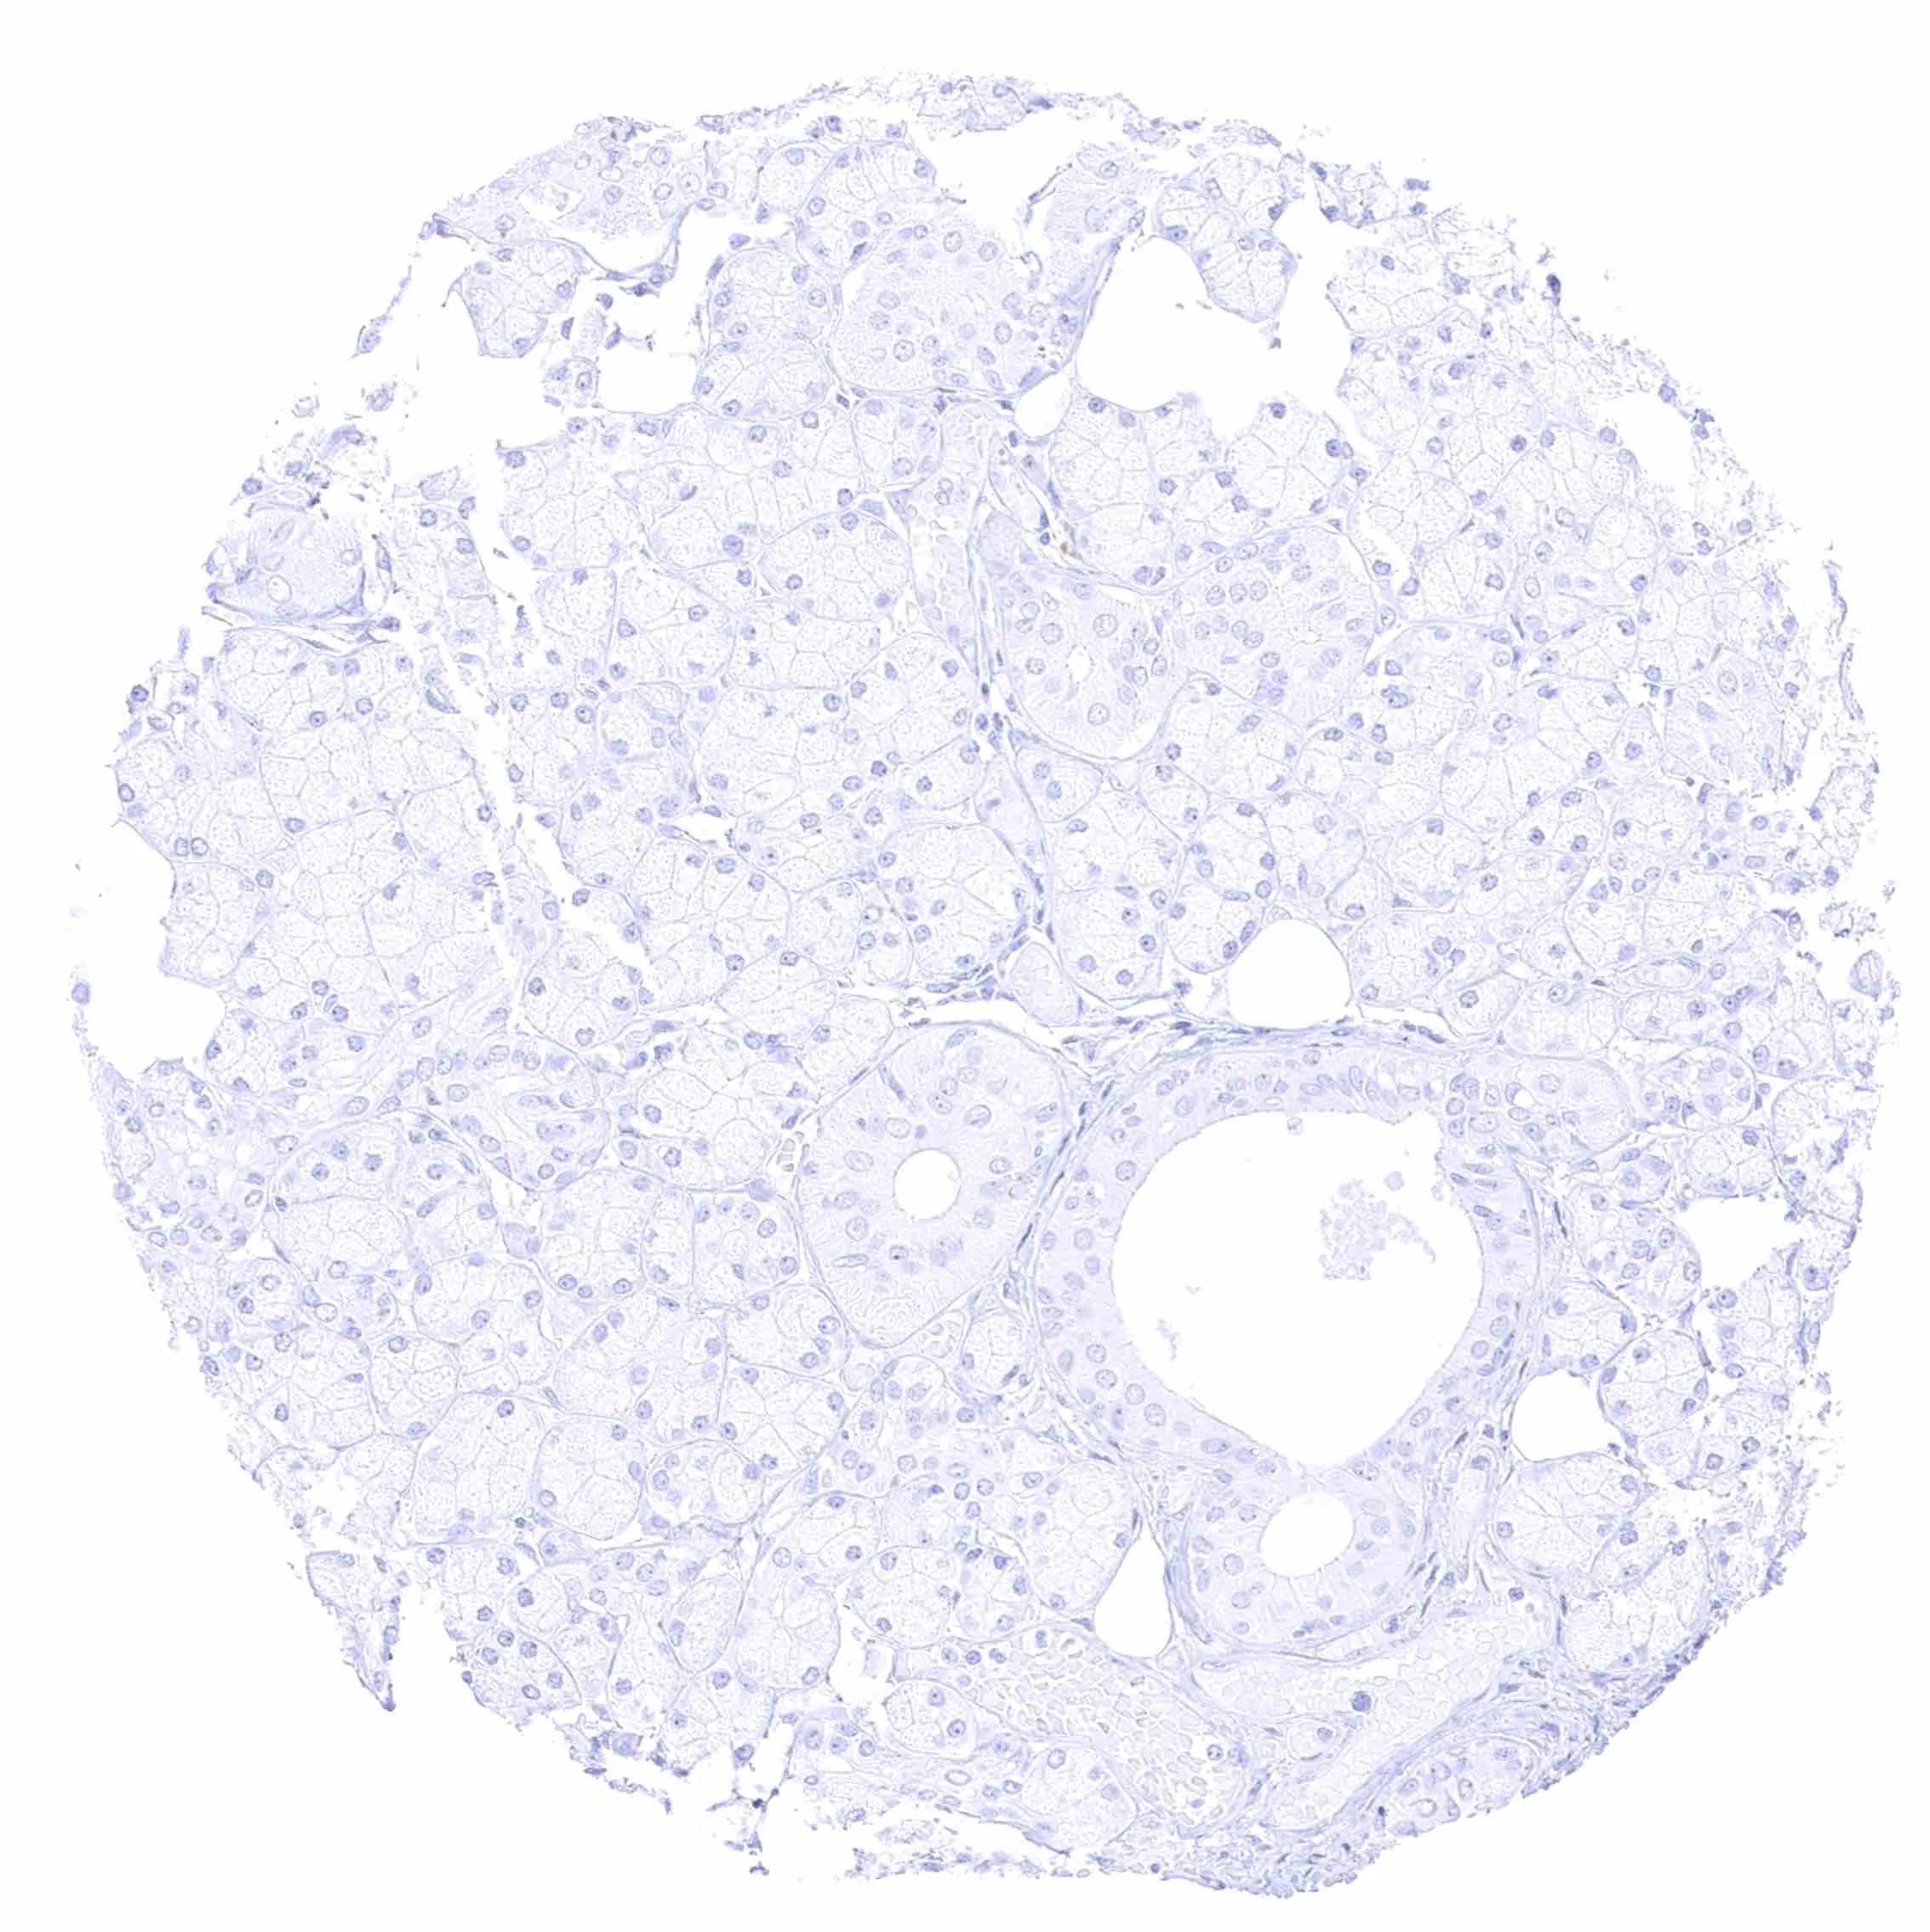

Liver